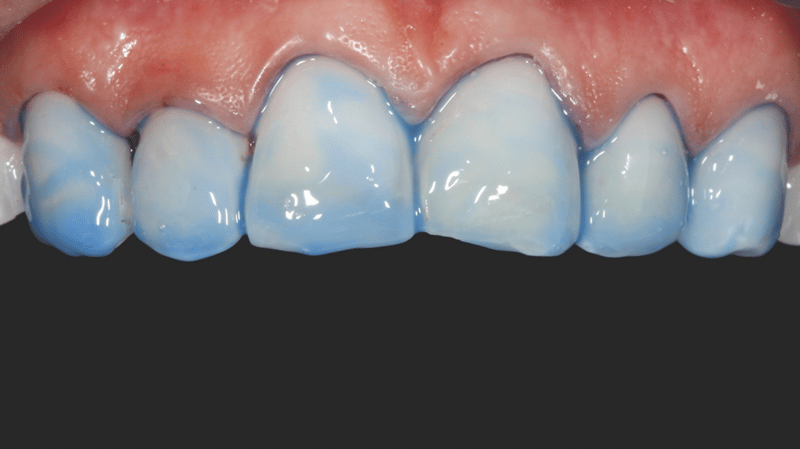

Eine junge Frau in den 20ern stellte sich in der Praxis von Dr. Jaleena Fischer-Jessop, DDS, MBA, vor. Sie hatte Verfärbungen im oberen Frontzahnbereich, welche durch ein Trauma verursacht worden waren und wünschte sich eine Lösung für ein ästhetischeres Lächeln. Die Behandlung der Patientin erfolgte mit einer konservativen und kostengünstigen Lösung: direkte Non-Prep-Veneers. Dr. Fischer-Jessop entschied sich für diese Vorgehensweise, um die Verfärbung abzudecken, die oberen Frontzähne der Patientin an die unteren anzugleichen und invasivere Methoden wie Implantate oder teure, im Labor hergestellte Veneers zu umgehen. Die Farben B1D und Enamel White (EW) wurden zur Aufhellung der Zähne verwendet. Das Transcend™ Komposit (Farbe „Universal Body“, UB) sorgte für einen natürlichen Übergang zwischen den Randbereichen und den zervikalen Bereichen.

- Finale Restauration: Endgültige Zementierung mit einer stabilen und ästhetisch ansprechenden Veneer-Versorgung.

- Faziale Anatomie: Verwendung von kugelförmigen und langen, dünnen Diamantbohrern zur Ausgestaltung der fazialen Anatomie. Erstpolitur mit Jiffy™ Natural Polierern. Hochglanz-Finish zum Erhalt der tertiären Anatomie mit Ultradent™ Diamond Polish Mint und Jiffy™ Goat Hair Brush (in Europa nicht verfügbar).

Ergebnis und Reflexion

Mit dem durchgeführten Behandlungsprotokoll konnten die ästhetischen Anforderungen der Patientin erfüllt werden. Die Verfärbung der oberen Frontzähne wurde kaschiert und ein natürliches, auf die unteren Frontzähne abgestimmtes, Erscheinungsbild wurde erzielt. Die Verwendung von direkten Non-Prep-Kompositveneers war dabei eine konservative, höchst effektive Lösung, die sowohl den finanziellen Möglichkeiten der Patientin als auch ihrem Wunsch nach minimal-invasiven Methoden Rechnung trug.